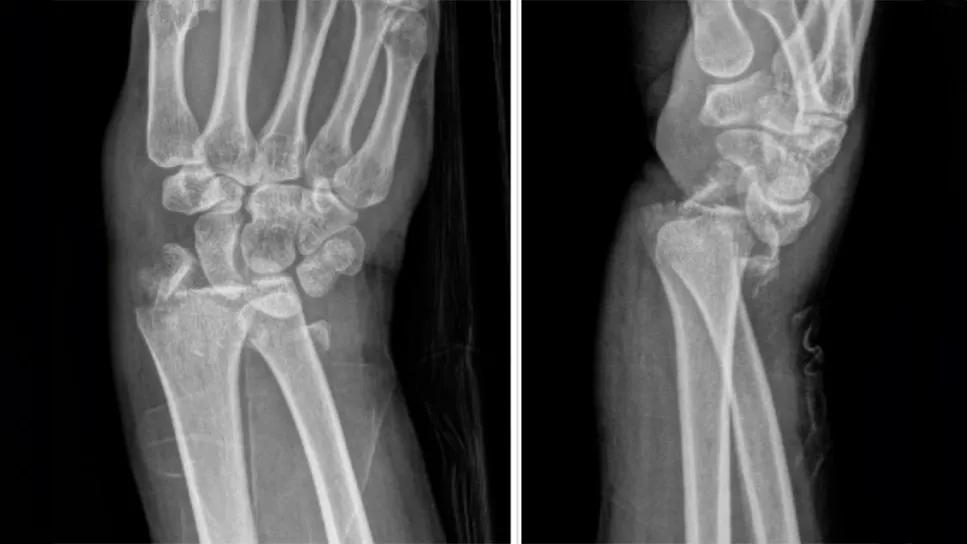

X-ray of a broken wrist

X-ray of broken wrist

Extra-articular fracture